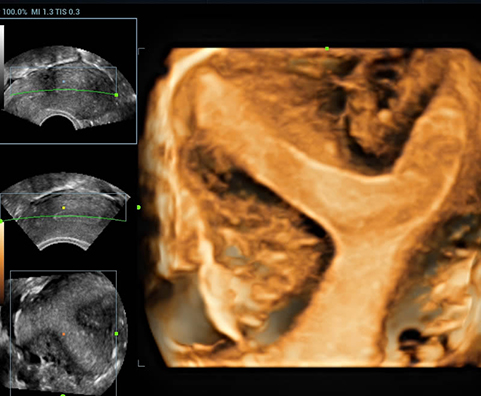

Внутриматочная перегородка, 3D